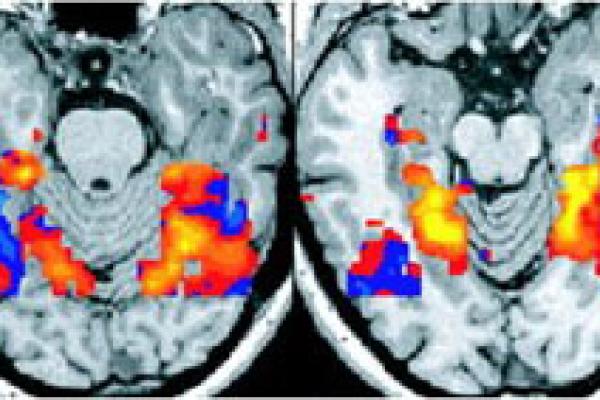

New ways of seeing with the INTEGRAL project

We ask the INTEGRAL team about their innovative machine learning approaches to understanding remotely gathered images, and the significant impact these technologies can have on the world.